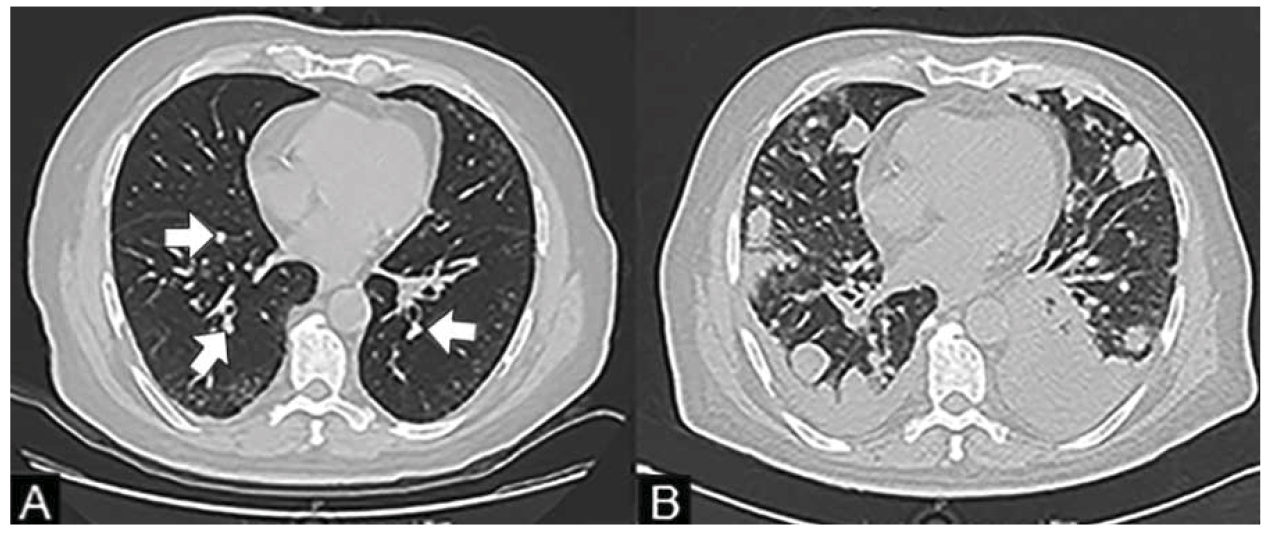

Como parte de su protocolo de estudio, se realizó una tomografía computarizada (TC) con contraste intravenoso de tórax, abdomen y pelvis, revelando múltiples nódulos pulmonares bilaterales de predominio periférico, con un diámetro promedio de 8 mm cada uno, sugestivos de enfermedad metastásica (figura 1).

Se solicitó valoración por Oncología médica, quienes refirieron que el paciente no era apto para recibir quimioterapia basada en cisplatino debido a su pobre estado funcional (Eastern Cooperative Oncology Group, ECOG 2). Por la misma razón, el departamento de Urología decidió no realizar una cistectomía radical y en su lugar mantenerlo en vigilancia estrecha, realizando nuevas RTUV según se ameritara como tratamiento paliativo. Dos meses posteriores a la cirugía, nuestro paciente fue hospitalizado debido a infección por COVID-19. La TC de tórax realizada en ese momento reveló derrame pleural bilateral, patrón intersticial y una rápida progresión de la enfermedad metastásica (figura 1B). Lamentablemente, murió debido a complicaciones relacionadas a la infección por COVID-19 y la enfermedad metastásica a los dos meses de realizado el diagnóstico.